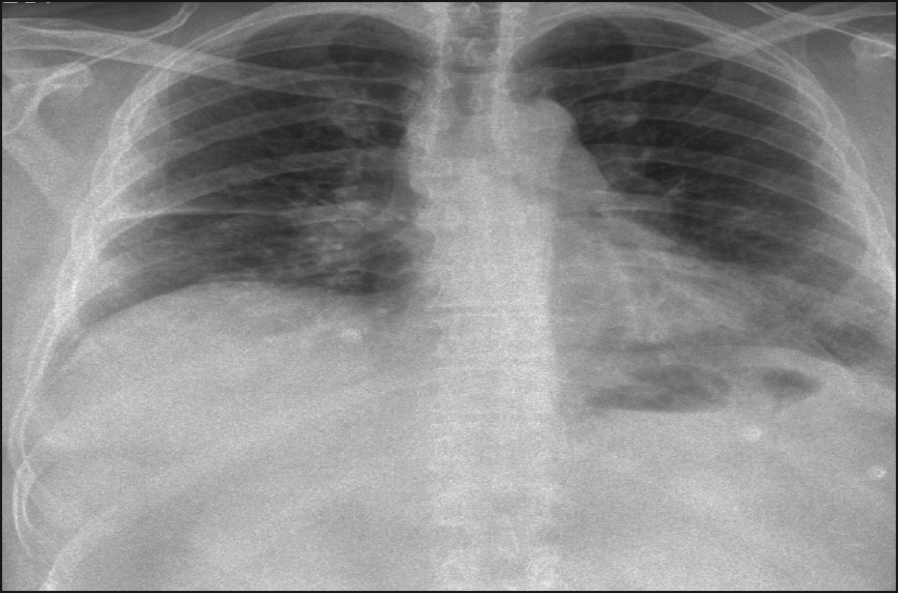

Figure 2. Bilateral ground glass opacities

High resolution computed tomography (HRCT) also demonstrated ground glass opacity involving both lungs (see Figure 2). The man was then booked for a bronchoscopy, which showed inflamed airways but no endobronchial lesions.